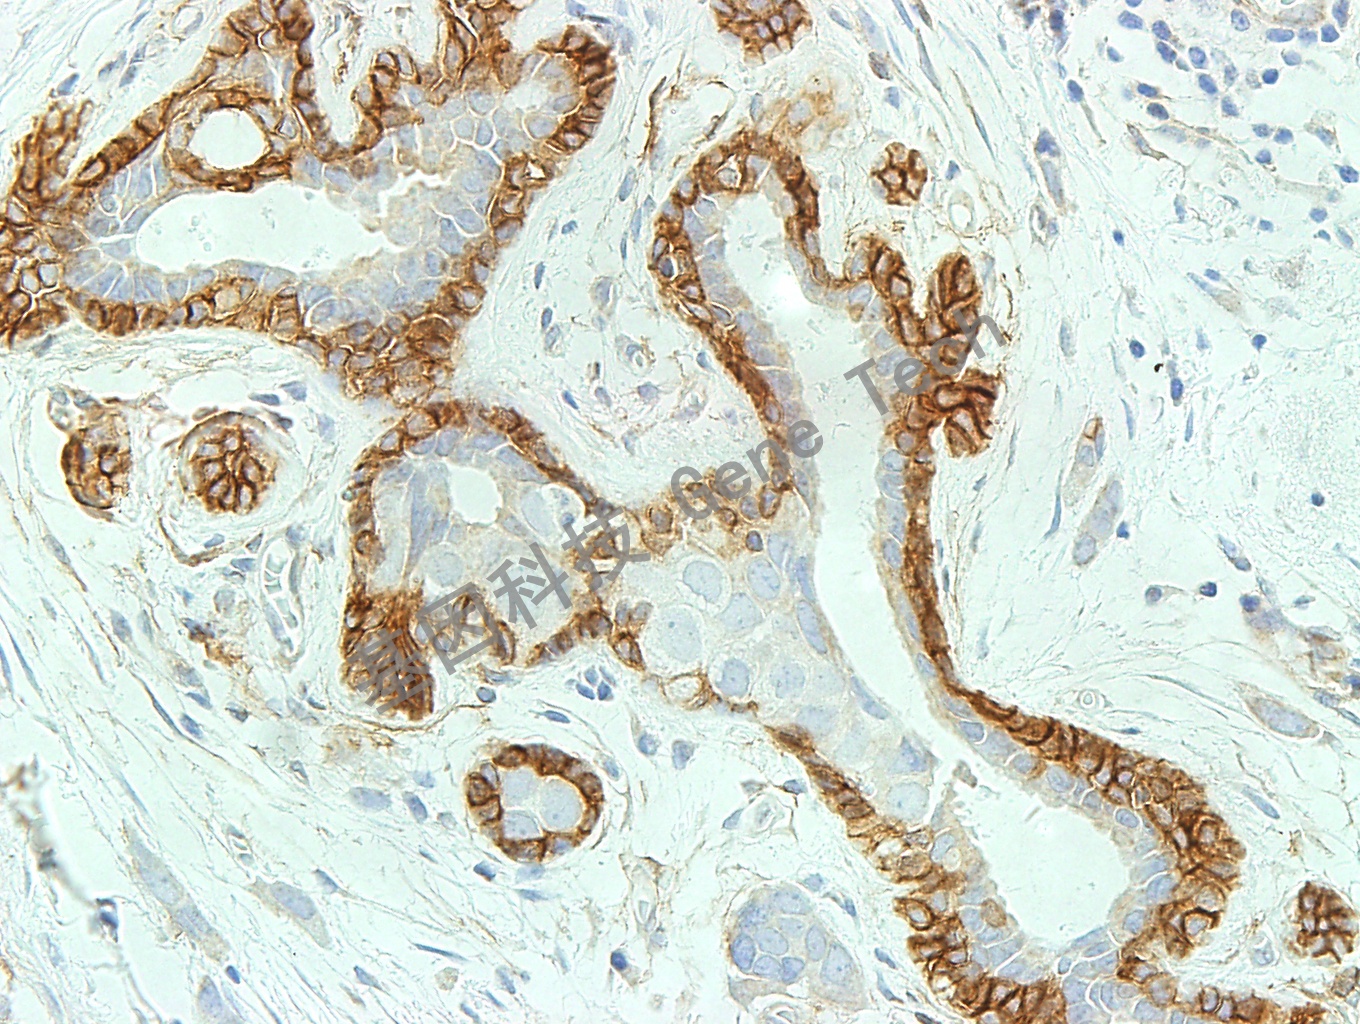

乳腺癌石蜡切片,用 NGFR(GT2258)染色,细胞浆阳性,DAB 显色。(10×)

乳腺癌石蜡切片,用 NGFR(GT2258)染色,细胞浆阳性,DAB 显色。(40×)